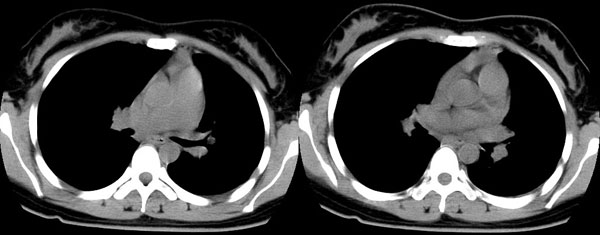

女性,25岁。反复咯血3年,再咯10天。外院x线胸片示:肺炎?支扩?

ct所见:左肺下叶基底段见大片状毛玻璃样改变,其内可见扩张细支气管。

ct诊断:考虑支气管扩张合并感染.

ct所见:左肺下叶基底段见大片状毛玻璃样改变,其内可见扩张细支气管及血管纹理影。后接正常描述。

ct诊断:左肺下叶支气管扩张伴出血。

胸部ct平扫所见:胸廓两侧欠对称,左侧略小,胸壁骨质结构完整。左肺下叶后、外基底段

见大片状毛玻璃样淡薄影,边缘渐淡,其内可见多个环形小囊状影。余肺野清晰,

肺纹理规则,气管支气管通畅,内壁光滑。心脏、大血管大小、形态、密度未见

明显异常,胸膜不厚、光滑,纵隔内未见明显肿大淋巴结。

诊断意见:左肺下叶大片状毛玻璃样淡薄影考虑支气管扩张伴出血。